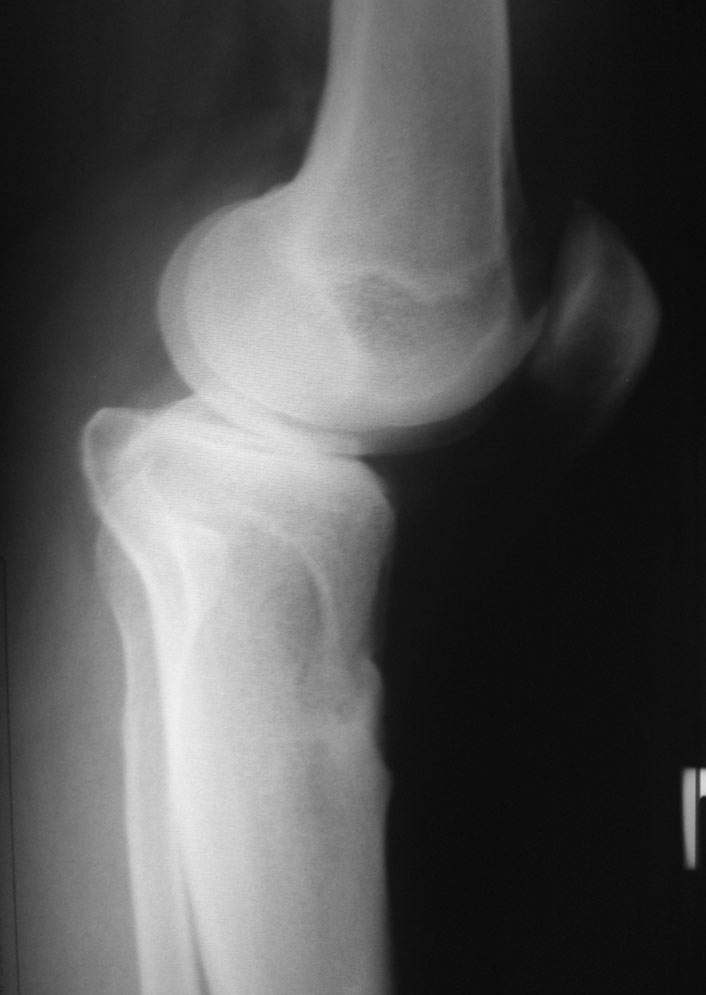

пациент наконец то объявился вновь и мы смогли выполнить новые снимки как лежа так и в нагрузке